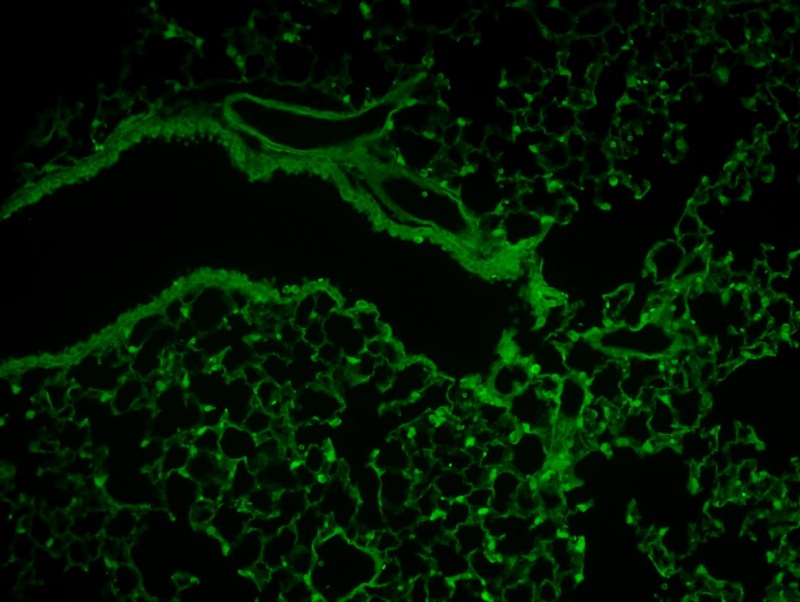

IL-33 expression in the lung as shown by citrine reporter